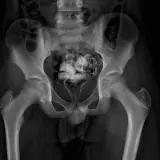

Over 2,100 interactive radiology cases, curated by radiologists for your level of training. Scroll, window, and view cases full screen — just like on PACS. Click linked findings in each writeup to jump straight to them on the image. Cases include sample reports, a focused discussion section, original illustrations, and videos.

PACSで期待されるツールを完備した完全インタラクティブな症例 — スクロール、ウィンドウ調整、ズーム、パン、計測、ROI、フルスクリーンモード。

重要な所見を症例画像上に直接ハイライトする豊富なアノテーション。症例解説内のリンクされた所見をクリックすると、スキャン上の正確な位置へジャンプできます。

アノテーション付きの画像所見とイラストで効率的に学習